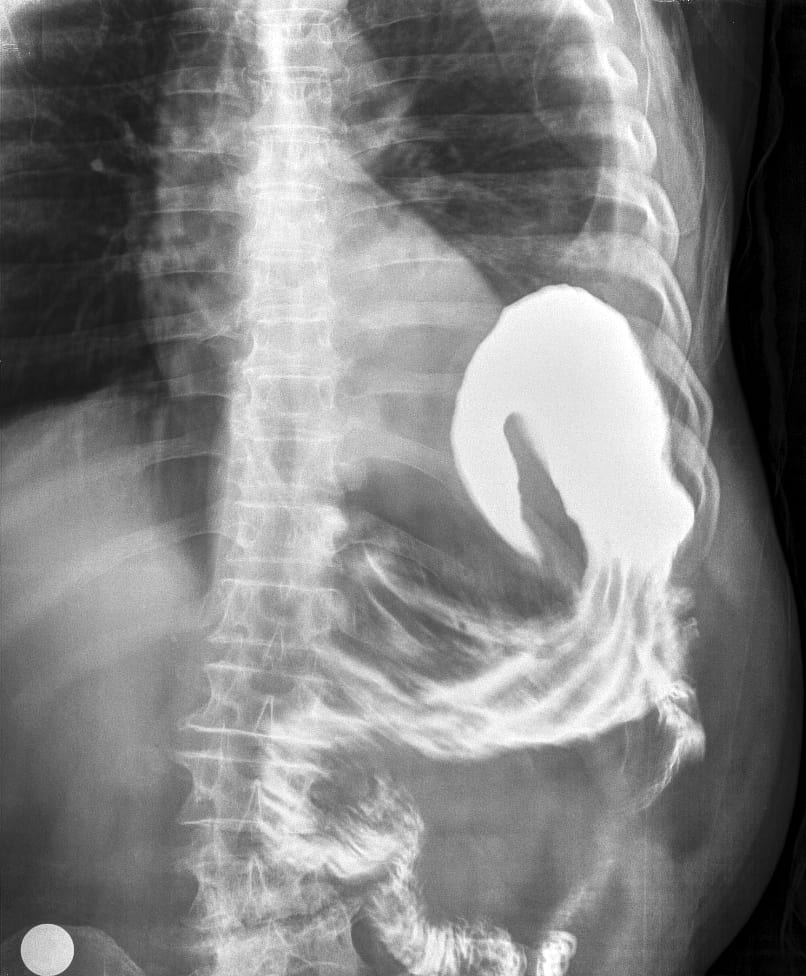

Xoắn dạ dày

Xoắn dạ dày - Ảnh 2

» Thông tin: Nam giới – 60 tuổi.

» Lâm sàng: Đau bụng cấp + Nôn.